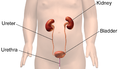

Difference between revisions of "File:ExcretorySystem.png"